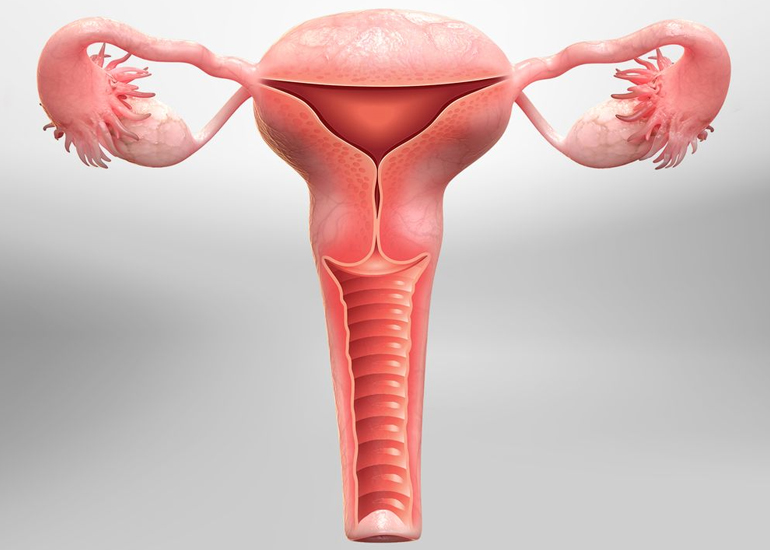

TREATMENT AVAILABLE FOR FOLLOWING DISEASES

Treatment Available